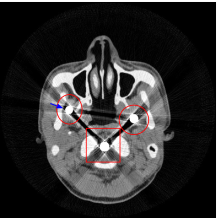

Figure 8 shows the reconstructed cerebral phantom from different methods. We highlight some regions with more distinct differences with red contours. Since the cerebral phantom contains more textures, it is more challenging than the NCAT phantom. The pros and cons of these methods are mostly the same as the previous example. However, we note that the reconstructed image from TV-FADM shown in Figure 8(e) has severe artifact, which is due to the well-known staircase artifact of TV regularization. We found that TV-FADM is relatively sensitive to the choice of its parameters. It is not easy to balance between sharpness of image features and metal artifacts reduction. The soft tissue around metal components is also not well preserved by the NMAR method as indicated by the blue arrow in Figure 8(d). Furthermore, the circled areas in Figure 8(d) show that there are still some artifacts around the metal. Same as the NCAT phantom, the proposed re-weighted JSR model has the best overall performance. Notice that the intensity of metals in Figure 8(d) and 8(f) seems lower than the rest of the reconstructed images. This is because we set the intensity of the metal components in the segmentation with the same mean value as that of bones. Increasing the value of metal components of can increase the intensity of metals in the reconstructed images, whereas it also introduces more artifacts around the metals.

Figure 12 shows a comparison between the reconstructed image from NMAR and the unweighted JSR model. Figure 13 shows a comparison between the reconstructed images from TV-FADM and the proposed re-weighted JSR model. Zoom-in views are provided in both Figure 12 and Figure 13 for a better visual assessment. As one can see that the reconstructed images from the unweighted JSR model and TV-FADM are less noisy than NMAR as indicated by the blue ellipse curve, whereas NMAR does a better job in preserving image features and suppressing metal artifacts. However, there are also new artifacts around the metal on the right as shown in Figure 12(d). The proposed re-weighted JSR model has best overall performance in terms of feature preservation, noise and metal artifact reduction.